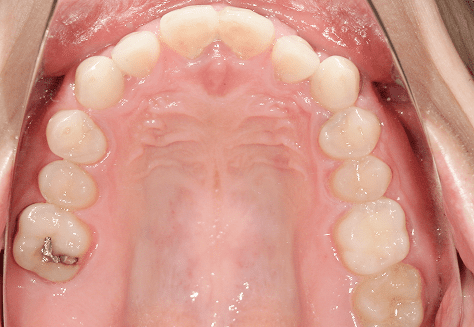

S.K

治療前

治療後

主訴

歯が重なっていて気になる。前歯が出ていて唇が閉じにくい。ハミガキがしにくい。

診断

上顎前突・叢生

年齢/性別

20代/男性

抜歯部位

上下第三大臼歯

使用装置

上下インビザライン

保定装置

上下ビベラリテーナー

診察料金

1,100円×33回

治療期間

3年5カ月